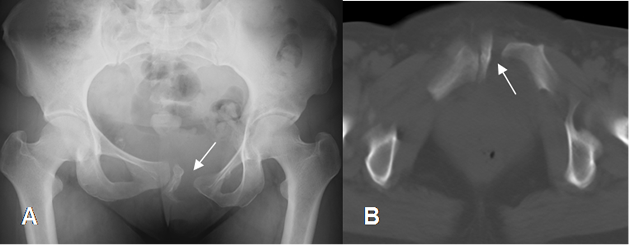

Fig 38. Trauma de pelvis.

A: Rx AP. Diastasis de la sínfisis púbica y sacroiliaca izquierda. (Flecha delgada). Hay luxofractura del pubis izquierdo, con hematoma en la pelvis, que comprime la parte posterior de la vejiga. (Flecha gruesa).

B: TAC corte axial. Luxofractura del pubis izquierdo.